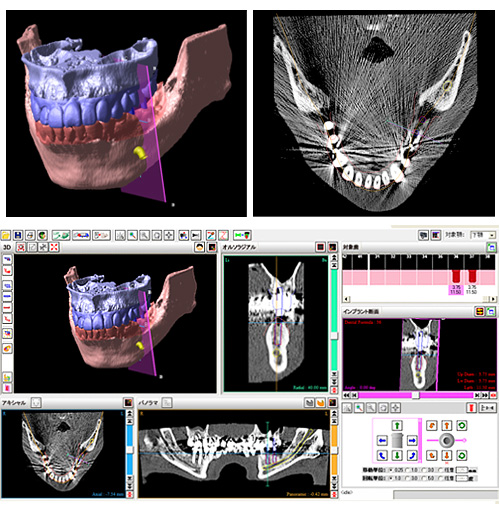

歯科用CT(3Dレントゲン):より確実で、安心できる治療のために

外科手術を伴うインプラント治療を行う際、診断はとても重要です。

通常、歯科医院で撮影をするレントゲン(オルソパントモグラフィー)では、2次元的で、顎骨の断面形態は正確に把握できません。当院では、手術を安全、正確に、しかも迅速に行えるように、CT(3Dレントゲン)撮影を行い、分析、カウンセリングをしています。

CTの活用により、顎の骨量、骨の厚さ、神経や血管、上顎洞の位置を正確に把握することができ、より確実で安心できる治療が可能となります。